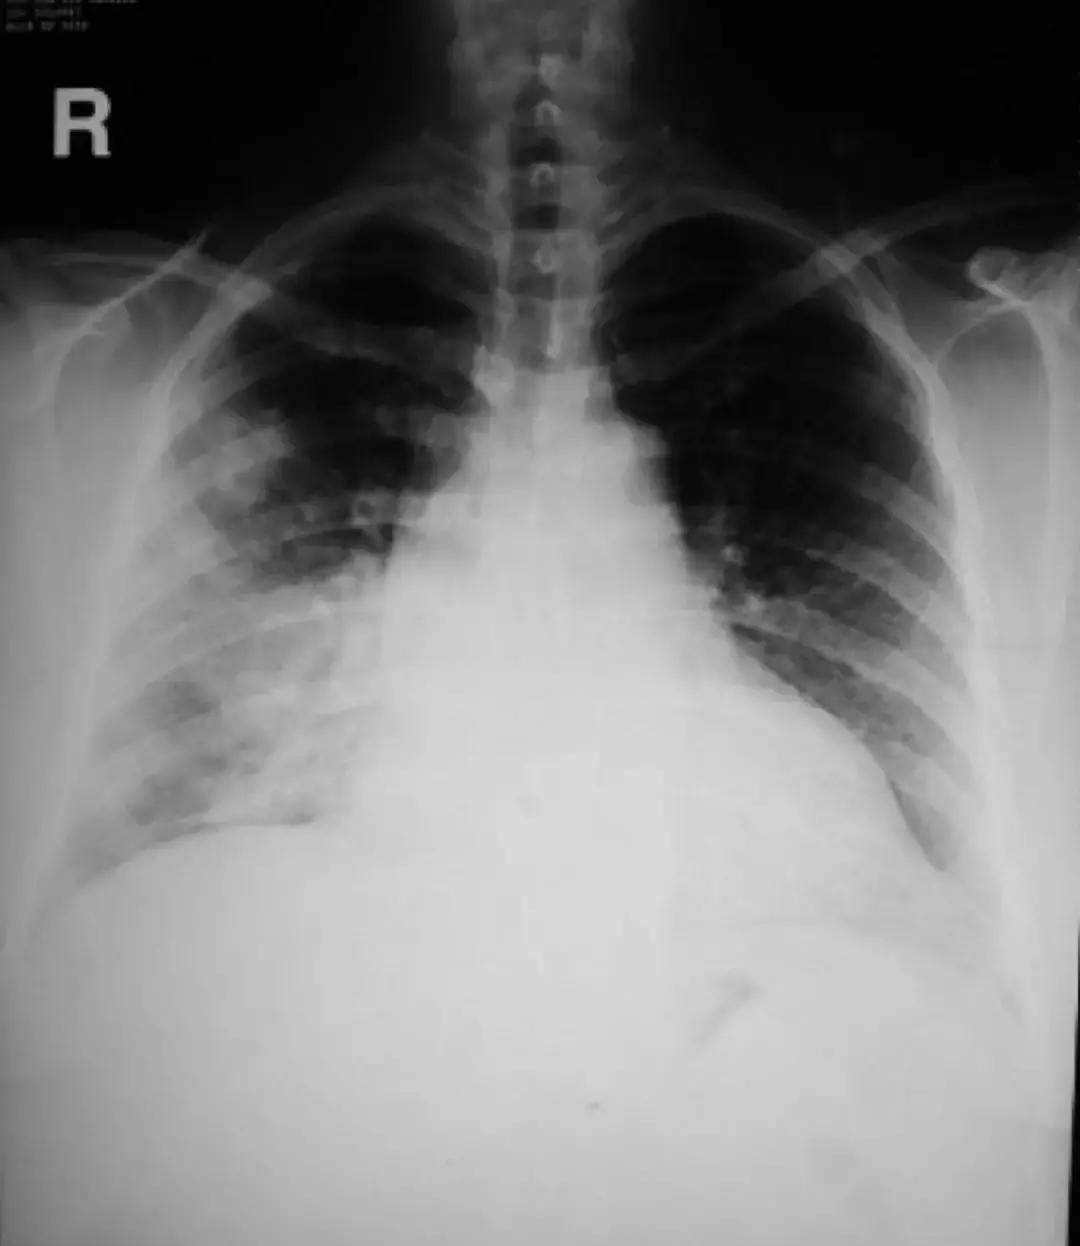

针对肺部感染的诊治来说,细菌、病人、抗菌药物、医生……到底谁是赢家?一切皆有可能!所谓「谍影重重」,就是胸部CT上的各种影像,一提到胸部CT,大家最容易想到的就是下图中在临床上最常见的影像学图像:

这种影像绝大部分是肺炎,在基层医院肺炎最常见的治疗方法是抗菌药物、皮质激素、维生素。